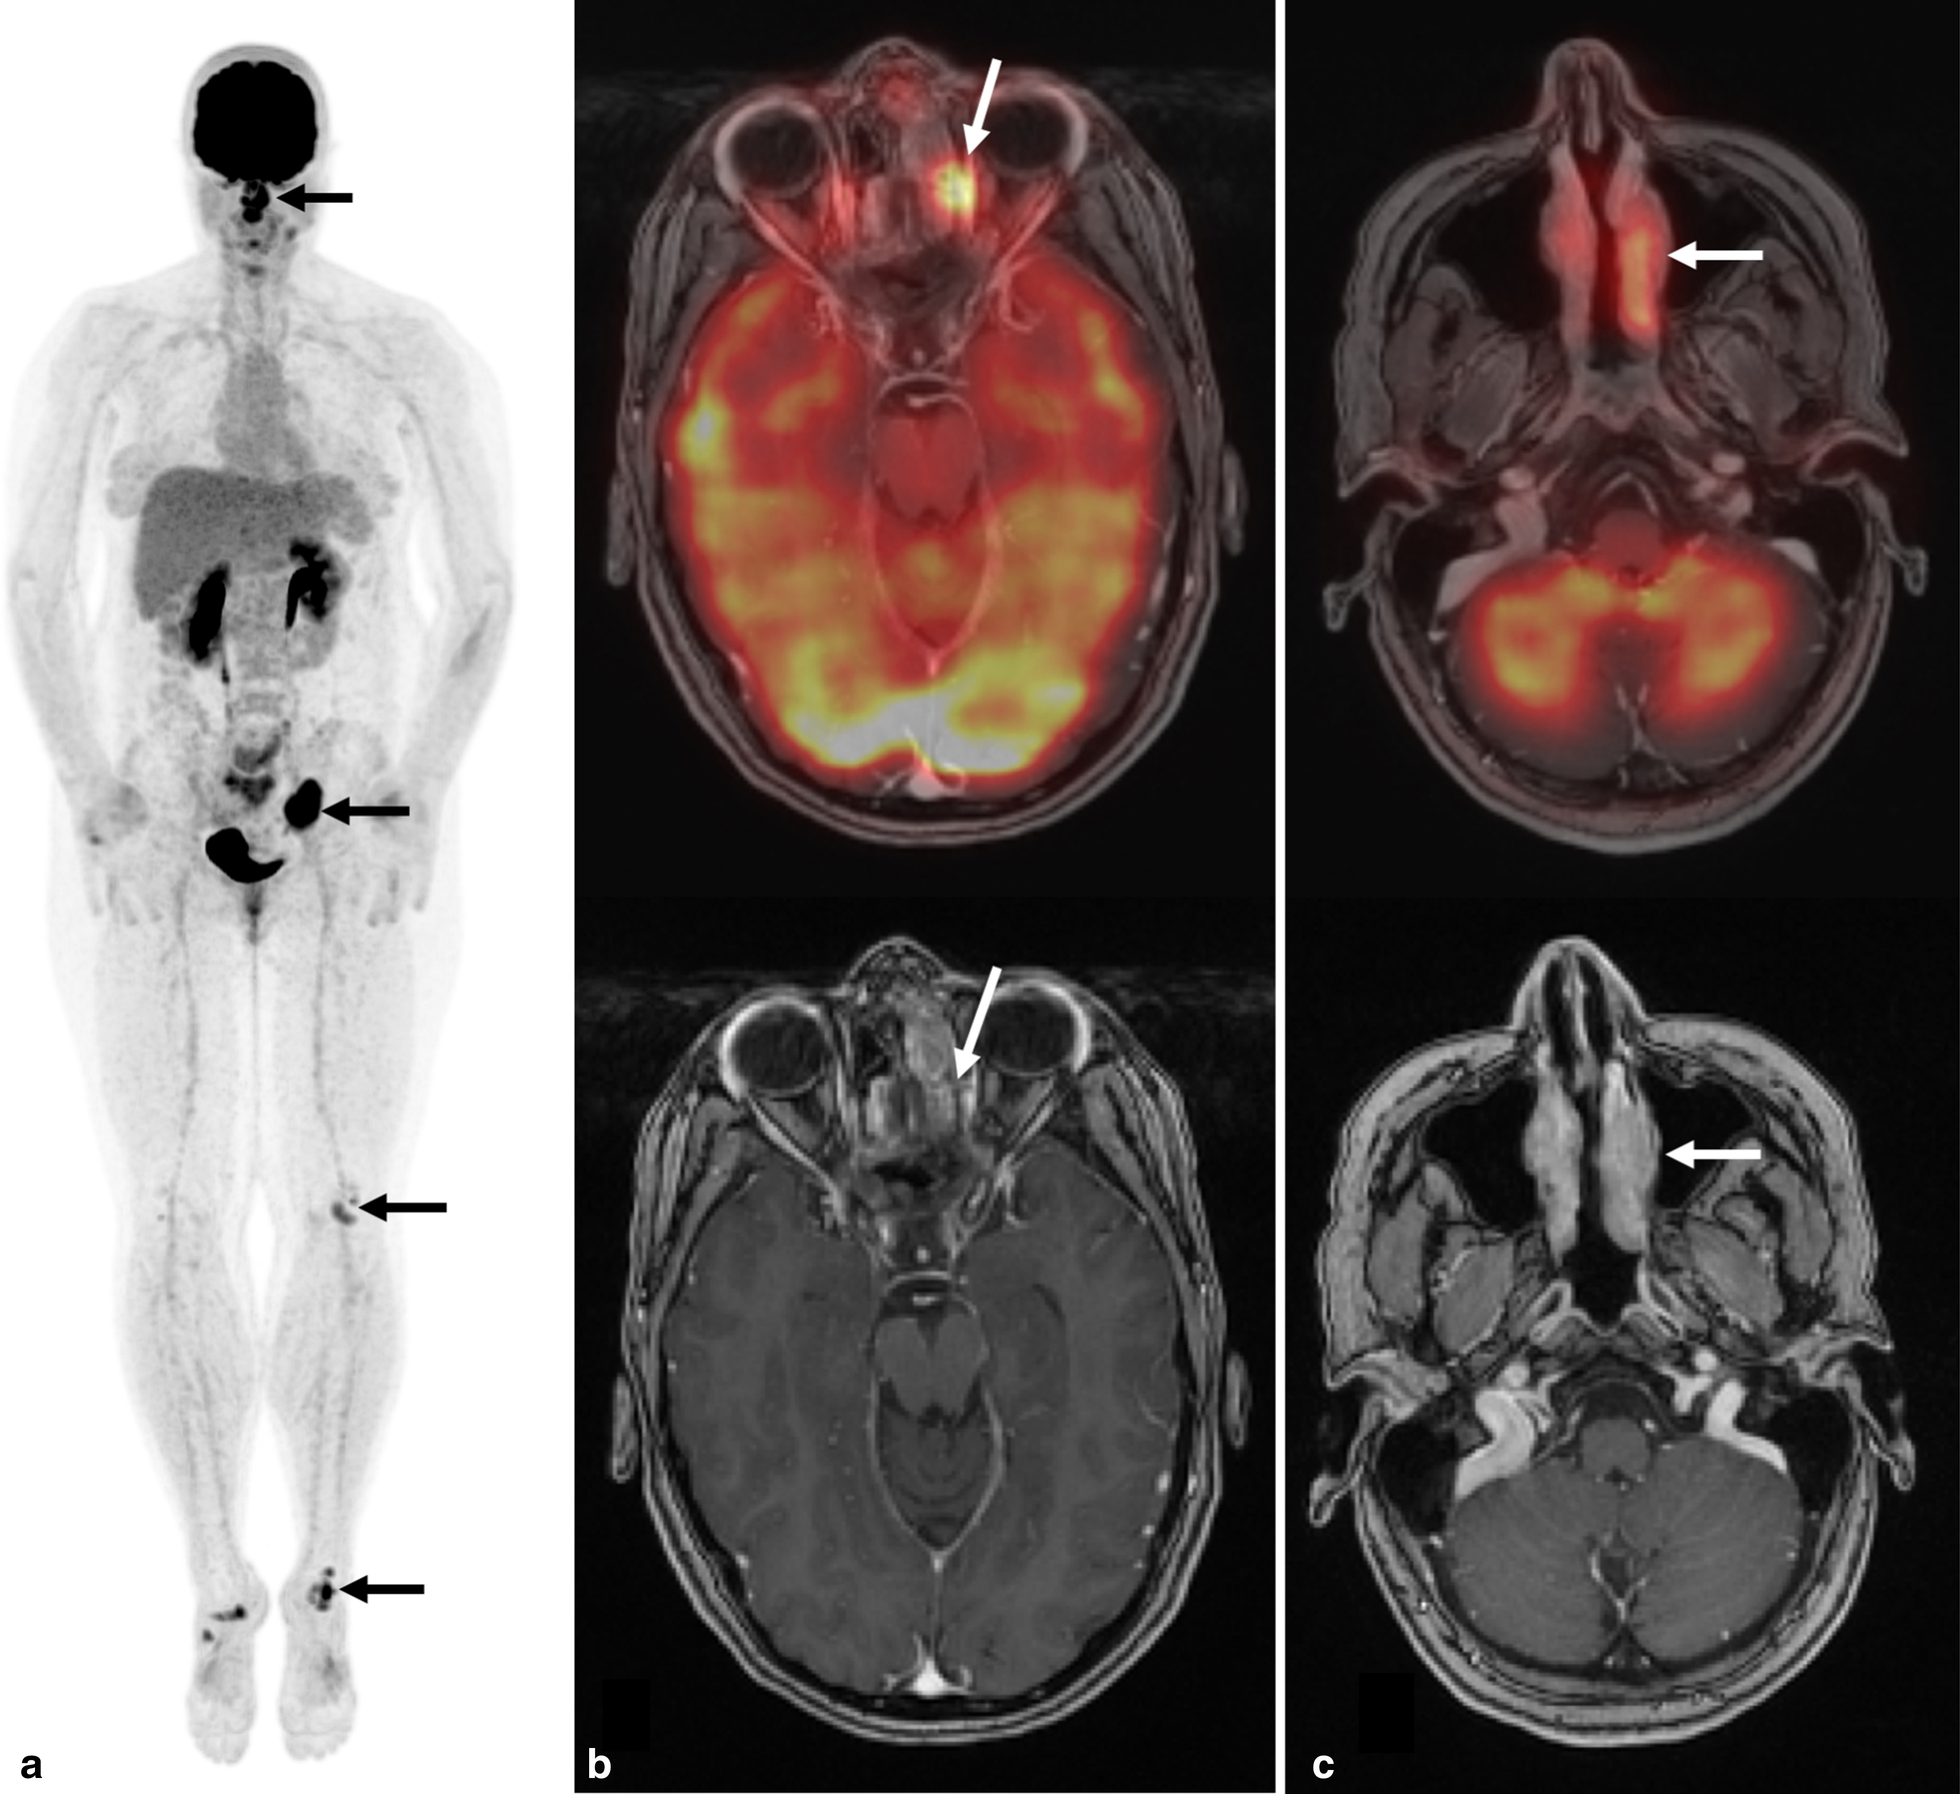

Fig. 2

Whole-body 18F-FDG PET co-registered with contrast-enhanced maxillofacial MRI demonstrates sinus lesions. a Whole-body FDG PET maximum intensity projection image demonstrates intense uptake in the nasal cavity, paranasal sinuses, left pelvis, left knee and left ankle (black arrows). Nonspecific mild uptake in the right ankle, and left side of the neck are also seen. b Mildly enhancing infiltrative lesion in the left anterior ethmoidal sinus in the Gadolinium-enhanced maxillofacial MRI, demonstrates intense FDG uptake in the fused PET/MRI axial image (SUVmax 10.6, white arrow). c Enhancing infiltrative mass in the left middle nasal turbinate, in the Gadolinium-enhanced maxillofacial MRI, demonstrates intense FDG uptake in the fused PET/MRI axial image (SUVmax 7.7, white arrow)